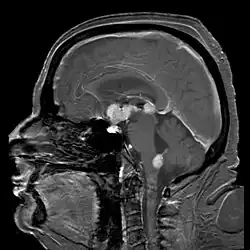

| Linfoma de células do manto, um tipo de linfoma não Hodgkin, onde se observa os contornos irregulares do núcleo das células do linfoma | |